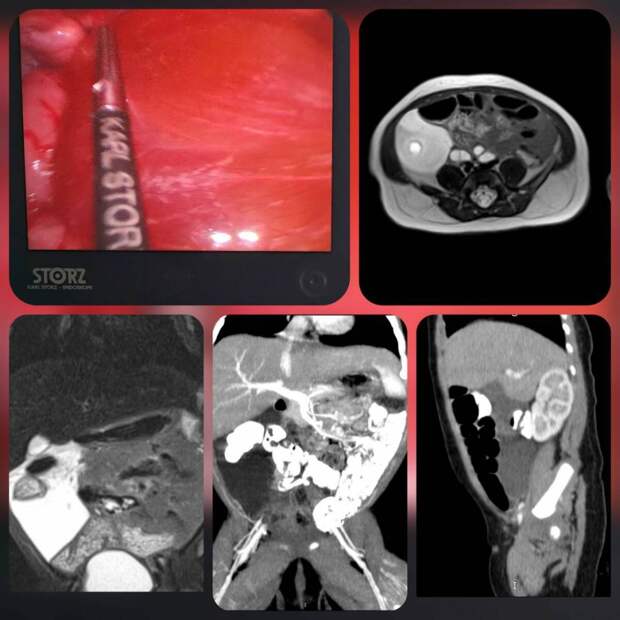

Ребенка срочно госпитализировали в отделение хирургии детей раннего возраста с крупным кистозным образованием в брюшной полости, которое выявили на УЗИ.

После комплексного обследования специалисты подтвердили редкую аномалию развития лимфатических сосудов в брыжейке толстой кишки.Консилиум врачей, вместе с заместителем главврача Михаилом Поспеловым и профессором Ильдаром Нурмеевым, принял решение о необходимости хирургического вмешательства

Хирурги Мария Зыкова и Буй Вьет Анх выполнили малоинвазивную операцию – лапароскопическое удаление лимфатической мальформации, с сохранением сосудов брыжейки толстого кишечника. Чтобы предотвратить повторное появление заболевания, внутреннюю поверхность лимфатических кист обработали специальным раствором, формирующим полимерное покрытие, препятствующее образованию лимфы

«Описанный случай является крайне редким. Чаще всего подобные образования обнаруживаются в области шеи и подмышечных впадин. По статистике, такие случаи встречаются примерно в 4 на 100 000 госпитализаций. Лечение крайне сложно из-за высокого риска осложнений: воспаления, перфорации, компрессии соседних органов и лимфоистечения», – объяснили в пресс-службе ДРКБ.